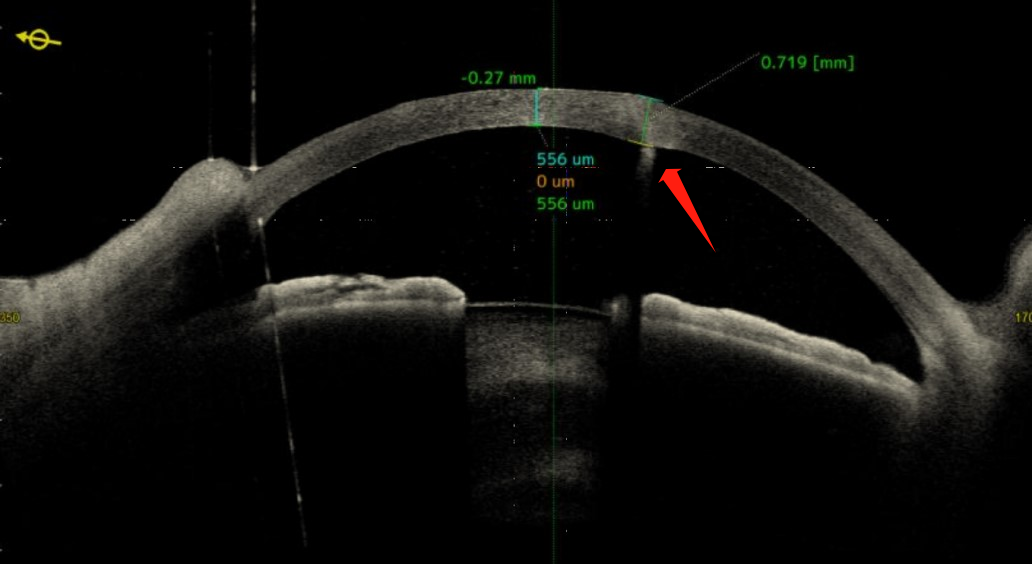

在裂隙燈顯微鏡下,透過斑駁的角膜傷痕和水腫區(qū)仔細查找,林琳醫(yī)生發(fā)現(xiàn)了隱藏在角膜潰瘍深處的2根刺,而且有一根已經(jīng)穿透了角膜進入前房(見圖1、2)。

圖1:箭頭所示為刺樣異物入前房

圖2:前節(jié)OCT,箭頭所示為刺樣異物入前房